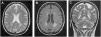

Patient 2A 43-year-old female was incidentally diagnosed with chronic kidney disease (CKD) on routine blood tests (creatinine: 2.9mg/dL, urea: 166mg/dL). By that time, the kidneys were small-sized and with undifferentiated renal parenchyma. Urinalysis did not show proteinuria or haematuria. The extensive laboratory analysis was inconclusive. Kidney biopsy was not performed for the same reason of the previous case. She started renal replacement therapy (RRT) after six years on follow-up. The patient presented with neurologic symptoms (neuropathic pain and decreased strength in the lower limbs, with a predominance of paresis in the right lower limb) one year before the CKD diagnosis. An MRI of the brain was preformed and revealed multiple, disseminated, hyperintense white matter lesions (WML) on the periventricular and subcortical areas (Fig. 1).

The manifestations of FD are nonspecific. Both our patients had unexplained renal insufficiency with mild or absent proteinuria, which is very atypical for the usual progression of the renal manifestations of FD. Normally, proteinuria is one of the initial kidney manifestations and it may initiate in the early teen years and more frequently during early adulthood. CKD progressively develops over time. The time of the presentation of end-stage renal failure in patient 1 is also highly unusual. Although, in an English cohort study of 98 hemizygous males, the mean age of ESRF was 37 years, the youngest ESFR patient presented at 18 years of age.16 One important limitation in our article was the unavailability of kidney biopsy, which we abdicated due to unacceptable risks without significant benefit. Patient 1 had only another trait of FD, LVH, but it may have other explanations like hypertension. As for patient 2, she has cerebral involvement with WML patent in the MRI and neurologic symptoms (paresis in the right lower limb and neuropathic pain in both lower limbs). Although these manifestations have some factors that do not fully fit in FD, no other explanation for them was identified despite thorough investigation.